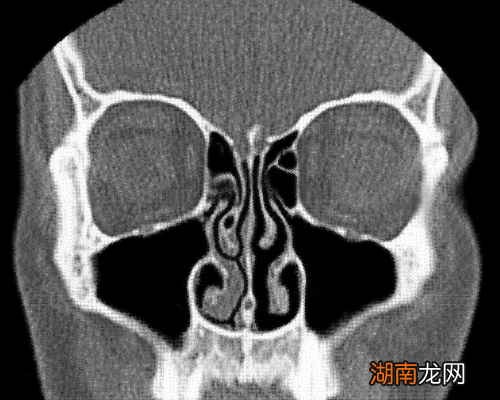

鼻子远非被动的通道 , 它隐藏着不断变化的内部结构 。正如埃克尔斯所说,鼻子内部有静脉勃起组织,其结构“与阴茎的勃起组织相似”,并且会充血 。感染或过敏会加剧肿胀,以至于鼻腔会完全堵塞 。

在健康的鼻子中 , 鼻腔组织的肿胀和消肿通常遵循一个称为“鼻周期”(Nasal cycle)的可预测模式 。每隔几个小时,一侧的鼻子会部分充血,而另一侧会打开 。随后它们交替进行 , 来回来回 。

在某种程度上 , 我们都是自己鼻塞不可靠的叙述者 。当患者前去接受检查时,医生可能会看到他们一侧鼻子明显比另一侧更肿胀,但这未必是患者感到更堵塞的那一侧 。“这仍然让临床医生感到困惑 。”史密斯告诉我 。其他因素,比如温度,也可能起到一定作用 。鼻子的内部结构复杂而神秘 。下次我如果再次病倒 , 再次感到堵塞时,我会思考所有这些事情 。